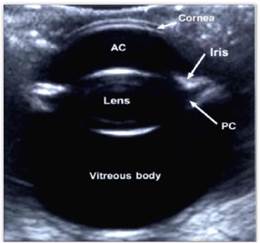

Cuando se habla de ecografía ocular es importante realizar comparación del ojo contra lateral, siempre que sea posible, diferenciando las distintas estructuras oculares como lo son: cornea, cámara anterior, lente (cristalino), cuerpo ciliar, cámara posterior, cámara vítrea, retina y nervio óptico (Figura 9) 10. Además de realizar diferentes cortes: longitudinales, transversales y axiales que permitan diferenciar posibles anormalidades, su ubicación y medida.

Comparando con el caso clínico, y de acuerdo a lo reportado en la bibliografía se puede observar que el ojo izquierdo está ecográficamente normal (Figuras 10 y 11), ya que se identifican todas las estructuras anatómicas normales, sin ningún tipo de alteración.